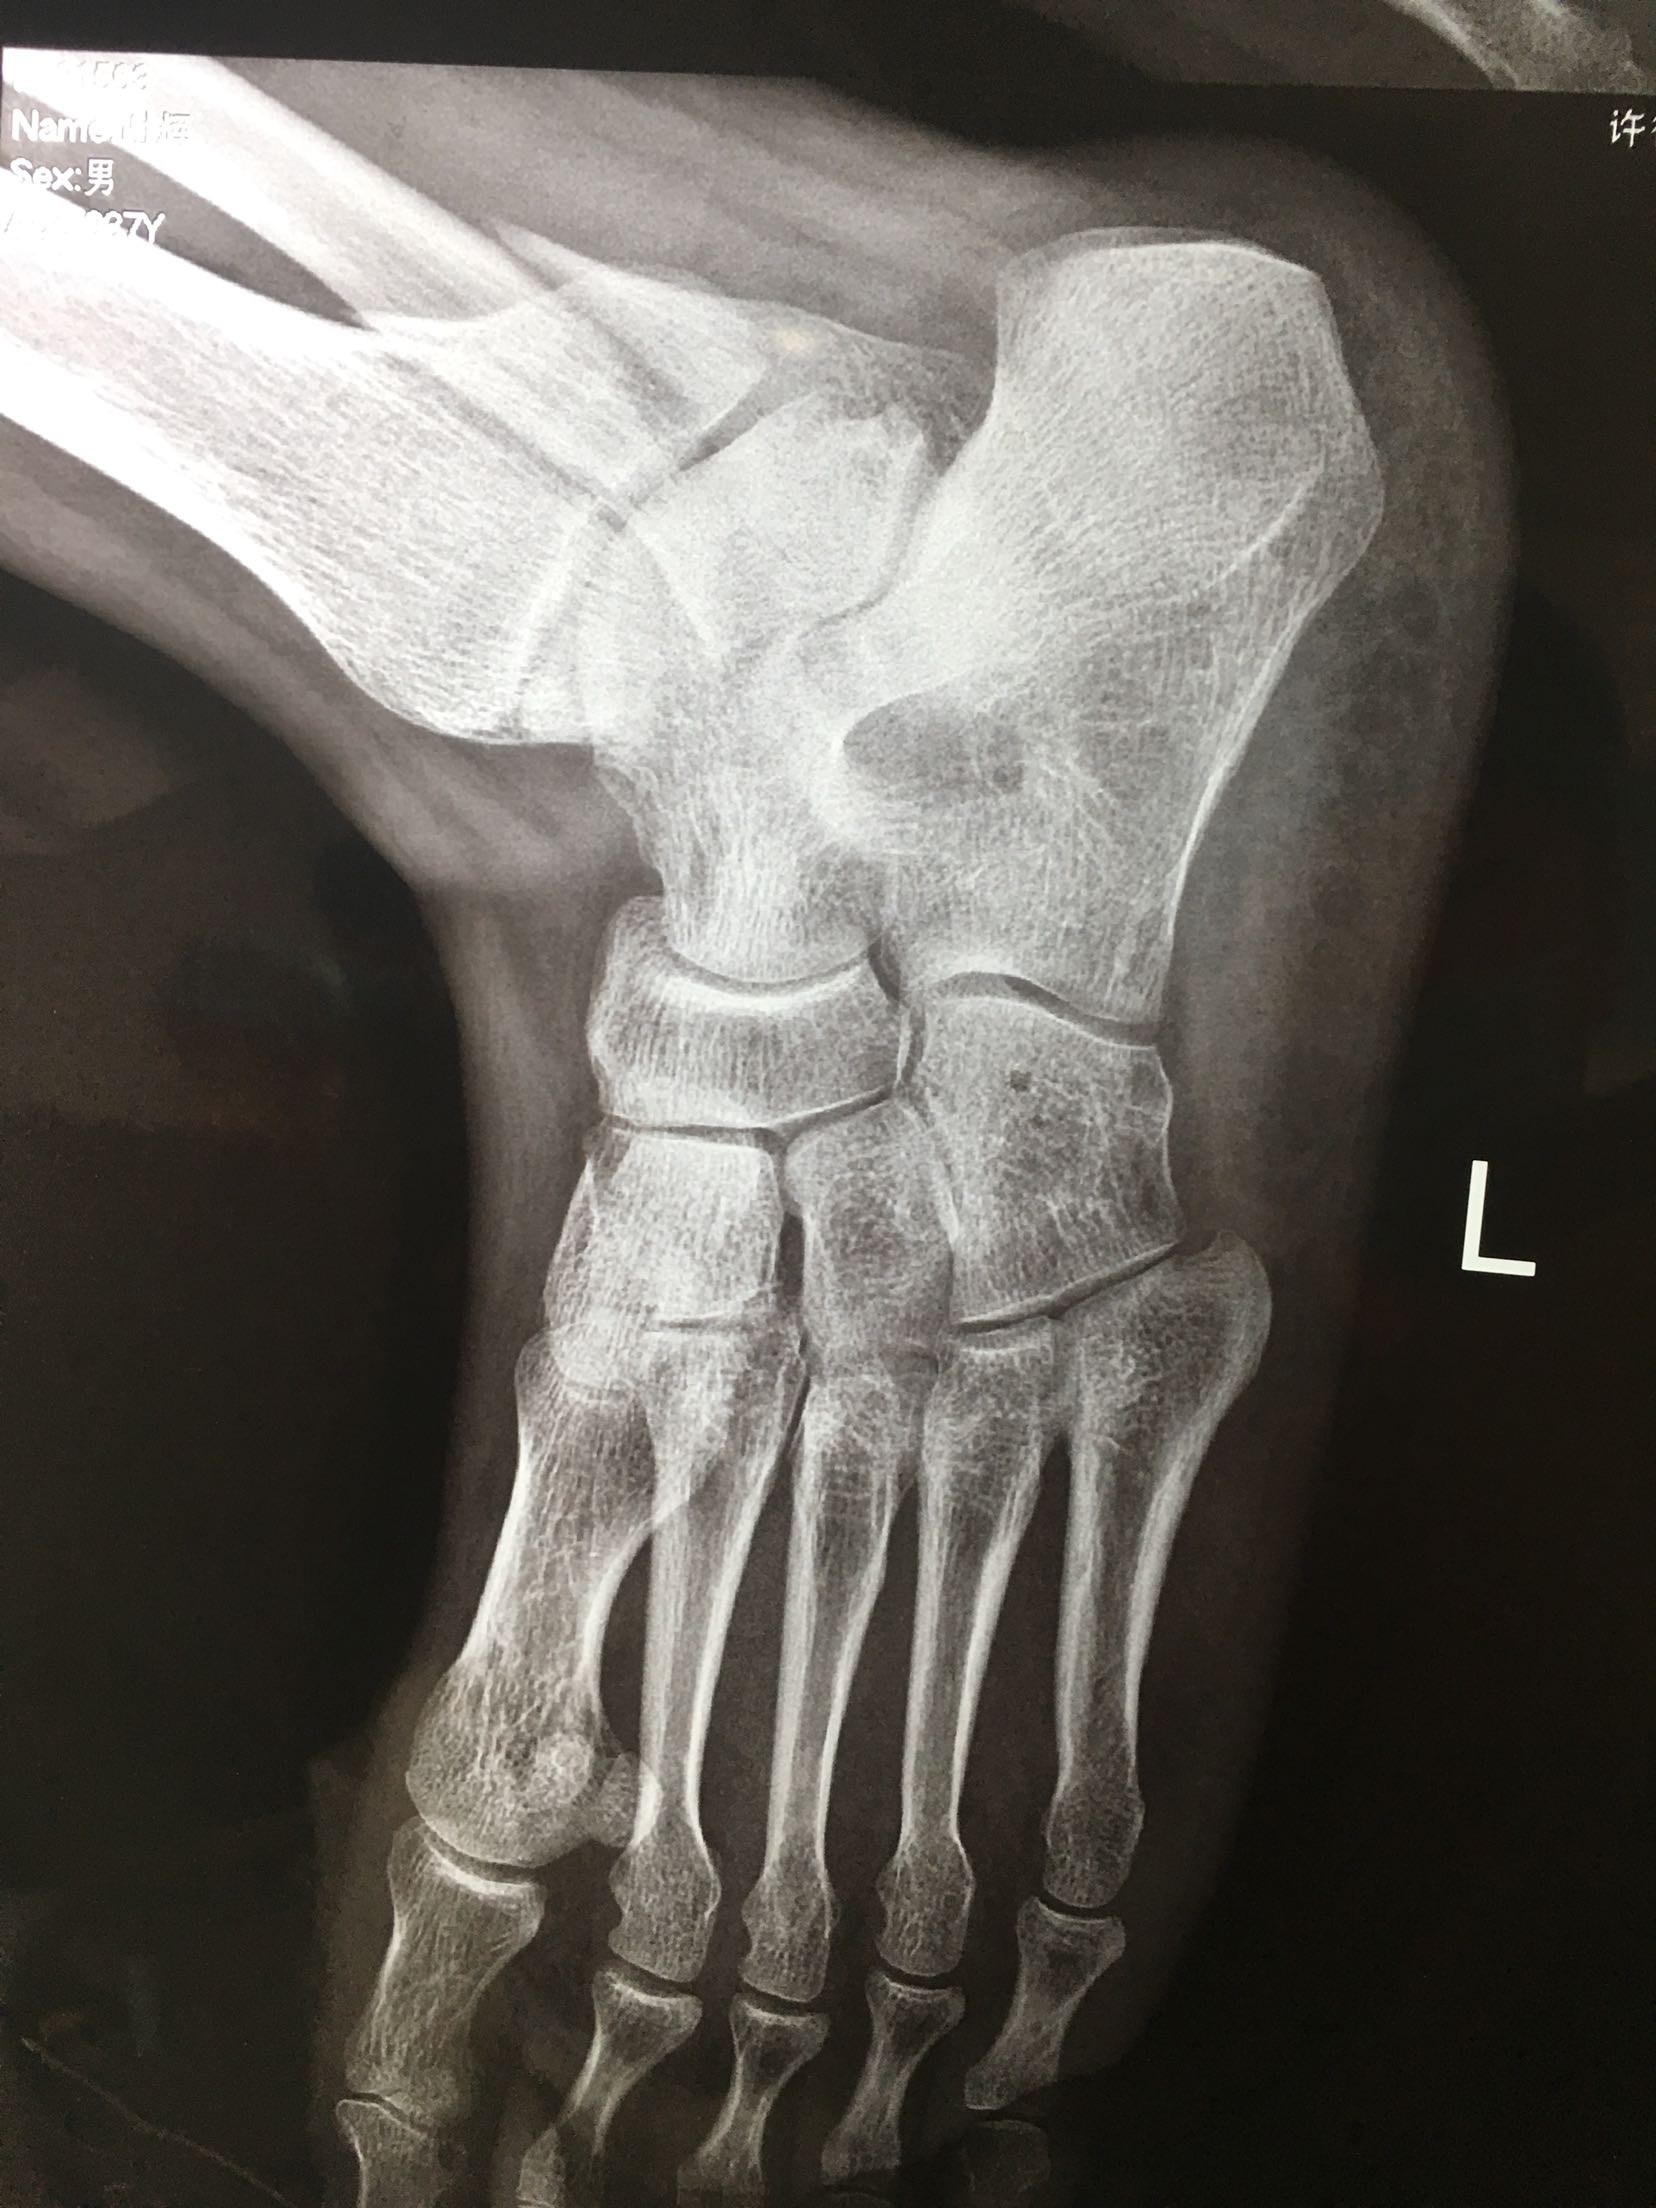

三踝粉碎性骨折(切复内固定)

患者,男,37岁,摔伤后右踝肿痛,畸形,活动受限3小时入院。既往身体健康,无特殊不良嗜好。

右踝部肿胀明显,局部皮色发红,皮温高,畸形,环形压痛,纵叩痛,末梢血运感觉正常,余未见异常。

急诊行跟骨结节牵引,术后一周肿胀消退,在腰麻下行切复内固定术,术后制动抬高,抗炎,消肿等对症处理。